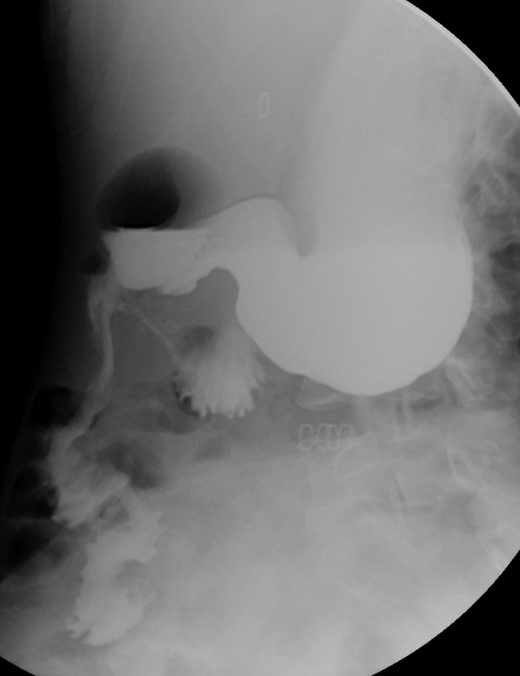

Contrasted intestinal series—distended stomach with delayed gastric emptying and reduced passage of contrast at the third portion of duodenum.

Initially, conservative management was adopted with some improvement of patient’s nutrition condition. However, as symptoms persisted, surgical treatment was recommended. Our surgical approach was a laparoscopic duodenojejunostomy with a latero-lateral stapled anastomosis between jejunum (30 cm from Treitz’s angle) and the second portion of the duodenum (Figs 5–9). The patient recovered with no pain but with a delay in diet acceptance. An upper GI contrast study was performed on the fifth post-operative day revealing a distended stomach with gastric emptying delay, but with unobstructed anastomosis, therefore without stenosis or leaks (Fig. 10). She was discharged home after 8 days with liquid diet and digestive transit restored. After 3 months of follow-up, the patient gained some weight and remained asymptomatic.